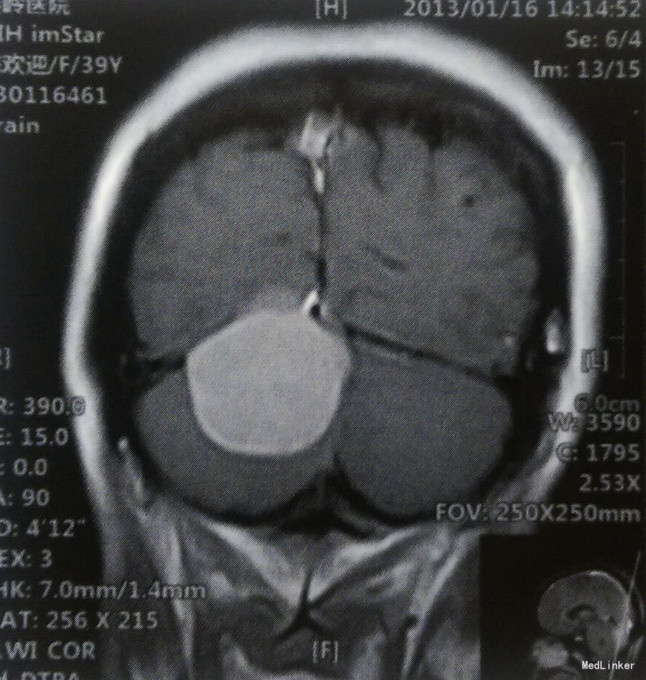

患者,女,39岁,已婚。主因间断头痛、头晕1年,加重1个月入院。 患者于1年前无诱因偶发头痛,以左颞部为著,呈钝痛,伴头晕,夜间休息时明显,打喷嚏时加重,自行口服“止痛药”效果不佳。1个月前上述症状加重,双颞侧头部闷痛明显,前往当地医院就诊,行头颅MRI检查:小脑幕下右侧小脑半球后方占位性病变,考虑脑膜瘤。未行任何治疗,门诊以“右侧小脑幕脑膜瘤”收入我科。既往体健,无其他相关病史。

体格检查:神经系统查体未见明显阳性体征。 术前影像学检查 头颅MRI检查:肿瘤边界清楚,T1WI呈等信号,T2WI为略高信号,信号均匀,病灶呈宽基底,与小脑幕及颅骨内板相连,增强扫描均匀强化,可见,“脑膜尾征”。

诊断:右侧小脑幕上下巨大脑膜瘤 治疗:手术切除